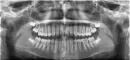

Видна ли на снимке убыль костной ткани?

Сегодня был у врача стоматолога. У меня возникла проблема в одном зубе. Показал для начала врачу панорамный снимок. Он взглянул на него и сказал, у меня пародонтоз, убыль кости. Меня это честно сказать ошарашило, так как никто никогда мне об этом не говорил. Да и возраст, наверно, для таких вещей не подходящий, мне всего лишь 25 лет. Врачей пародонтологов к сожалению в городе нет. Профессиональную чистку прохожу раз в 6-12 месяцев.

Действительно ли это похоже на пародонтоз и насколько всё плохо? По панорамному снимку, действительно уже есть убыль кости? Что можно предпринять в данном случае?

На ортопантомограмме определяется наличие восьмых зубов, для полноценного прорезывания, которых в зубном ряду места недостаточно. Как правило, их рекомендуется удалить.

Атрофия костной ткани незначительная. Такое состояние может быть вызвано перегрузкой.

Со стороны полости рта определяется гипертрофия слизистой и, похоже (для уточнения требуется клинический осмотр полости рта), который может возникать при несоблюдении техники чистки зубов или наличия вредных привычек.